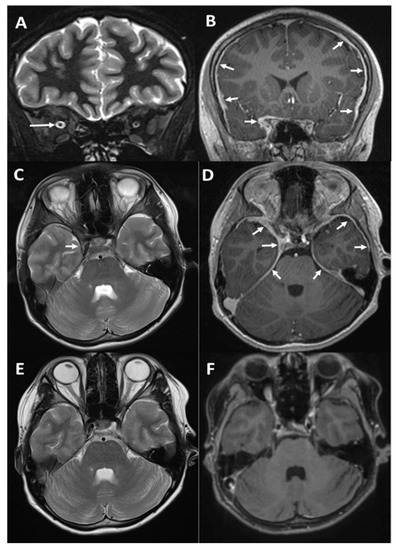

Idiopathic Hypertrophic Pachymeningitis: Does Earlier Treatment Improve Outcome?

Background/goal: Hypertrophic pachymeningitis is a rare chronic inflammatory disorder characterized by marked fibrous thickening of the cerebral and/or spinal dura mater. This condition has largely been reported in adults, but there are very few reports in children. Methods: We describe a 14-year-old boy [...] Read more.

Background/goal: Hypertrophic pachymeningitis is a rare chronic inflammatory disorder characterized by marked fibrous thickening of the cerebral and/or spinal dura mater. This condition has largely been reported in adults, but there are very few reports in children. Methods: We describe a 14-year-old boy with idiopathic hypertrophic pachymeningitis, who presented with deteriorating vision on a background of severe headache. We evaluated pediatric cases of hypertrophic pachymeningitis and compared treatments and their relation to outcomes. Results: There are only eleven pediatric cases of hypertrophic pachymeningitis reported in the literature. In the patients treated with steroids either at presentation or subsequent relapses, a good response was reported. In the cases with delayed initiation of steroid treatment, this was often related to an incomplete recovery. In our patient, this delay may have contributed to his poor visual outcome. Conclusions: Early initiation of steroid treatment in children with idiopathic hypertrophic pachymeningitis may improve outcomes. Full article

Show Figures

Figure 1